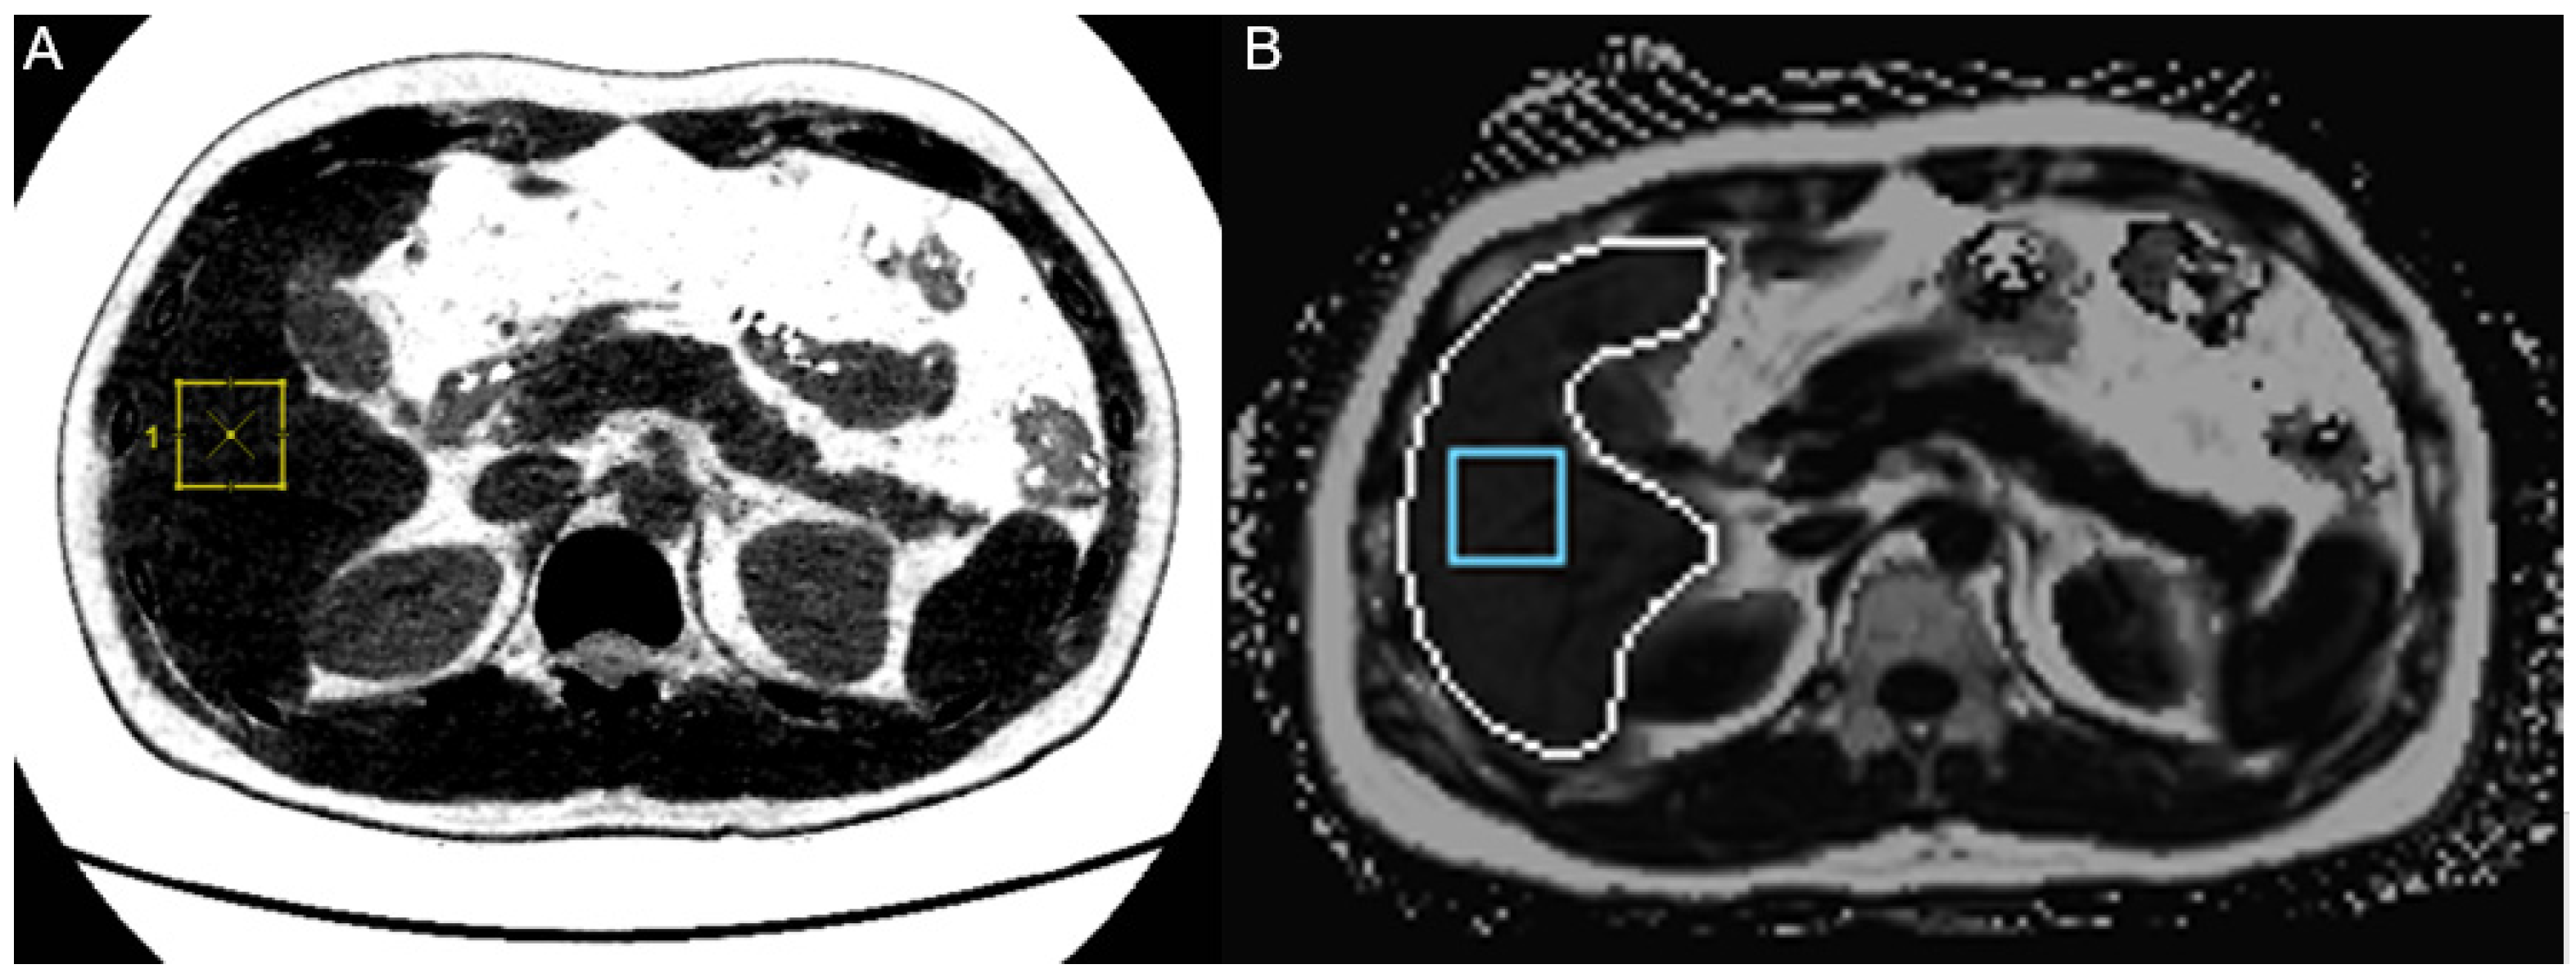

2.2.2. MRI-PDFF